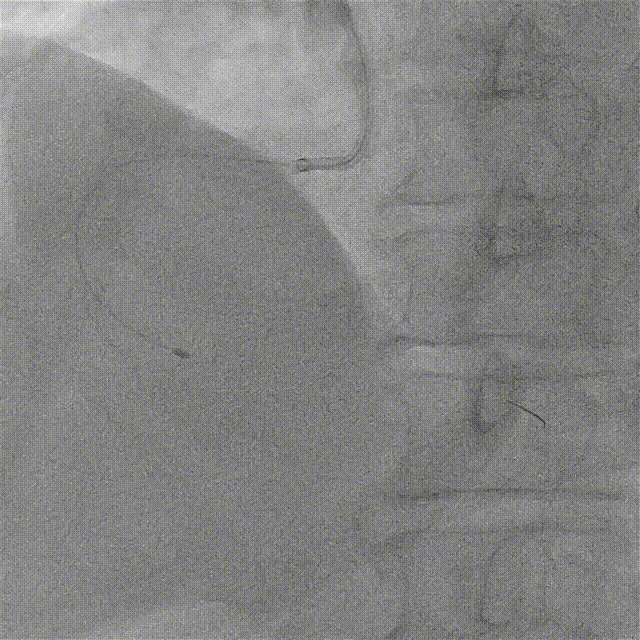

ROTA 1.5Burr再次旋磨远段

再次送入1.5mm旋磨头对远端病变进行旋磨,顺利通过病变处并进行充分打磨。